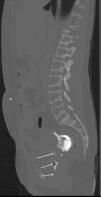

A 24 year old female patient was diagnosed with end stage renal disease during pregnancy. There was no other etiological factor, but hypertension. Patient was recommended 20hours of hemodialysis, but she refused and gave birth to a living child on the 38th gestational week. She has been on CAPD for the last 3 months. Since last week she has started to have abdominal pain accompanied with nausea and fever (>38°C). With these complaints she was referred to our policlinic and her peritoneal fluid cell count was found 4860/mm3 (95% polymorphonuclear leukocytes). Cultures were obtained and she was admitted to our hospital with the diagnosis of peritonitis. Blood analysis showed leucocytes 9000/mm3, hemoglobin: 8.8g/dl (11.5–16), C-reactive protein: 14.2mg/dl (0–0.5), sedimentation: 135mm/hour. Pseudomonas aeruginosa was detected in blood cultures. She was on empiric ceftazidime and cefazolin treatment and treatment was continued because P. aeruginosa was found sensitive to this treatment. Urine culture remained sterile. Patient stated that there is dialysate in her vagina. She was consulted with obstetrics and gynecology regarding any fistulas. A urine catheter was placed and it is understood that origin of dialysate was vagina. Contrast enhanced computerized tomography was done showing a vaginal fistula (Figs. 1 and 2). CAPD catheter was removed. Surgical operation was found unnecessary and hemodialysis was started. Patient was discharged after 3 weeks of ant biotherapy.

Patients on CAPD have an increased risk of both hernia formation and dialysate leakage as an intraperitoneal pressure related complications. One of the rare peritoneal fluid leakage is through processus vaginalis3 and main mechanisms include leakage through the fallopian tube and then the uterus and vagina, or leakage through a fistula between the uterus and the peritoneal cavity formed after surgery.3 One of the reason for fistula formation is peritonitis which is often caused by skin bacteria penetration via transvisceral, transvaginal or hematogenous spread of organisms, and the CAPD catheter can become colonized by bacteria creating a biofilm that repeatedly seeds the peritoneum.4

In our case, a rare entity; vaginal fistula and also another rarely seen clinic; peritonitis secondary to vaginal fluid were present. Probably secondary to the fistula, peritonitis developed and after peritonitis, fluid from fistula tract has increased and caused vaginal leakage.